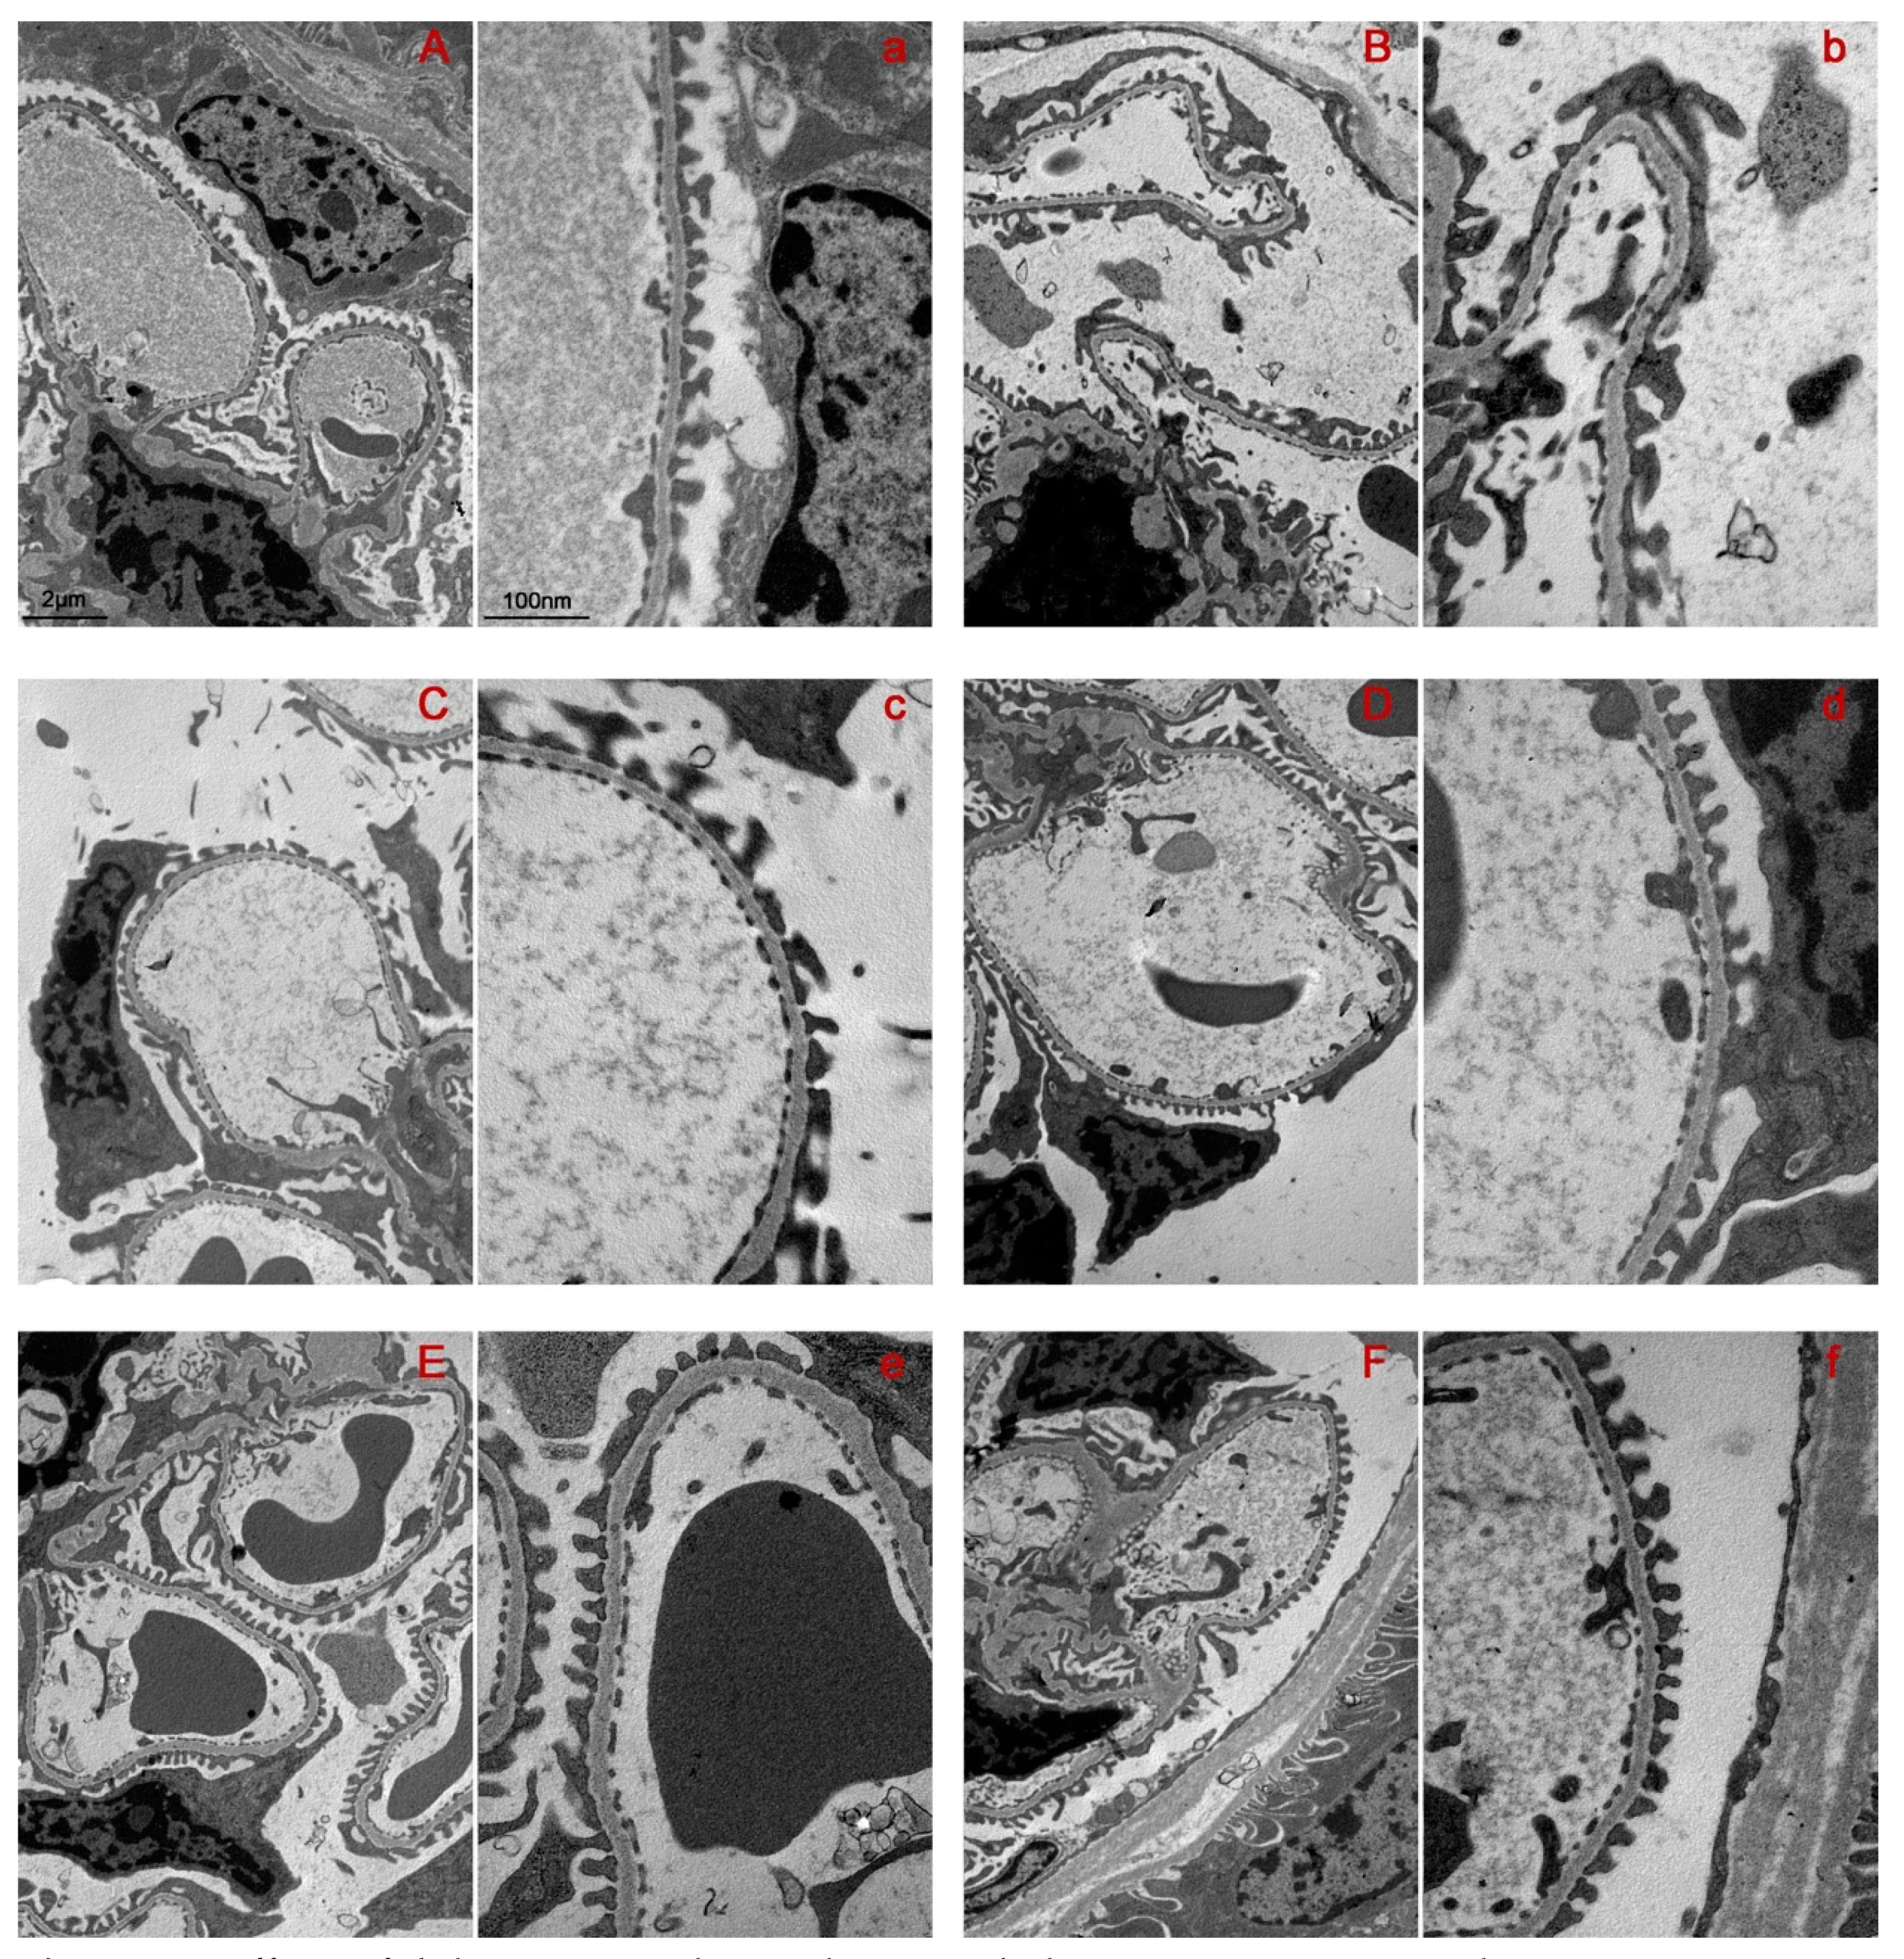

2.2. Bilastine Effect on Glomerular Structure Alterations

2.3. Bilastine Effect on Slit Diaphragm and Cytoarchitecture Protein Expression

4.6. Transmission Electron Microscopy